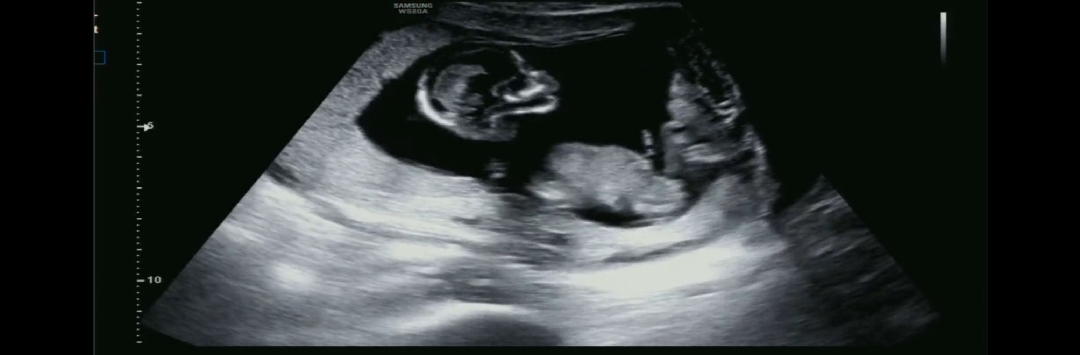

지금은 남녀 생식기가 튀어나와있는 시기예요. 사진상 다리뼈인지 생식돌기인지 확실친 않지만 각도를 보면 아들 같습니다.

13주차 아들 맞나요??ㅎㅎ

남편은 다리 사이에 보인다고 ㅎㅎ아들이라는데 많은 참견 부탁드려요 ㅎㅎ

이사진으론 보기힘들어요 오른쪽에태반때문에흐리게 나와서요ㅜ